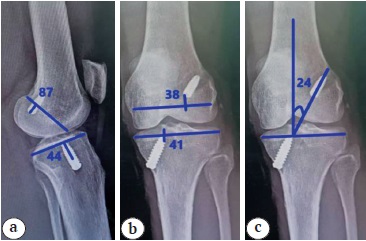

The selected cohort was subjected to radiological examination to differentiate anatomical and nonanatomical ACLR. Plain radiography of both knees in standing anteropasterior view with 0° knee flexion, pasteroanterior view with 30° knee flexion and lateral view with 30° knee flexion were taken. All X-ray images were interpreted in DICOM format in PACS (version 8.2). The anatomical nature of reconstruction was assessed as per the radiological landmarks described by L.A. Pinczewski et al. [9] (Figure 1).

Figure 1. Plain X-rays of the knee joint showing anatomical tunnel parameters and GIA: a — sagittal tunnel positions; b — coronal tunnel positions; c — graft inclination angle

Accordingly, the tunnel parameters analysed in the selected cohort were coronal femoral tunnel position, sagittal femoral tunnel position, coronal tibial tunnel position, sagittal tibial tunnel position and graft inclination angle (GIA). Patients found to have anatomical tunnel position and GIA were then subjected to final analysis (Figure 2). Those who were found to have nonanatomical tunnel position and GIA were excluded from the study.

Figure 2. A patient’s postoperative X-rays showing anatomical tunnel parameters and GIA: a — sagittal tunnel positions; b — coronal tunnel positions; c — graft inclination angle